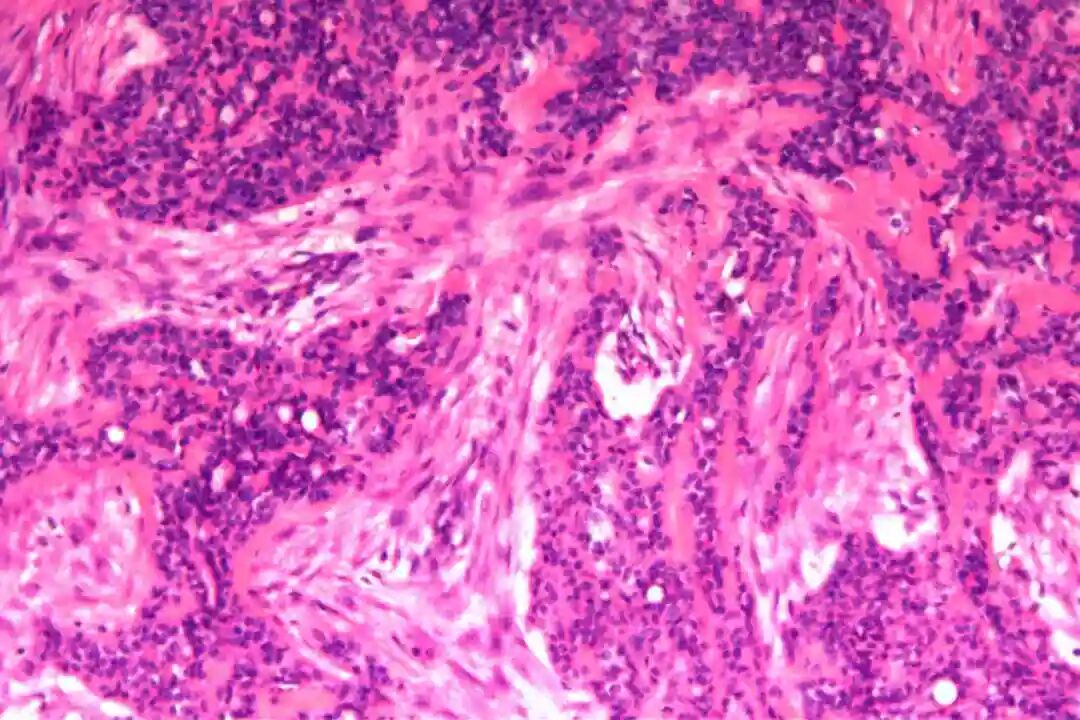

细胞形态:基底样肌上皮细胞体积较小,呈圆形或卵圆形,细胞核深染、染色质均匀,核仁不明显,胞质稀少、淡嗜酸性;腺上皮细胞体积略大,呈柱状或立方状,细胞核淡染、染色质疏松,核仁清晰,胞质丰富、嗜酸性。实性巢团内可见少量微小腔隙,腔隙内可含有少量嗜酸性或嗜碱性黏液样物质(PAS染色阳性),这是实体型与其他实性肿瘤的重要鉴别点;核分裂象少见,一般≤5个/10HPF,部分实体型区域可出现轻度至中度细胞异型性,但无明显恶性增殖活性表现,与高级别乳腺癌的细胞异型性有明显区别。

实体型区域与经典型区域无明显明确界限,相互穿插分布,实体型巢团可逐渐过渡为经典型的筛状或管状结构,两种区域的细胞成分相互延续,均可见腺上皮细胞与肌上皮细胞的混合存在,无明显细胞异型性差异(实体型区域异型性略高于经典型,但整体温和)。这种混合性形态是本病的重要镜下特点,也是与单纯实体型PACC、单纯经典型PACC的主要区别。